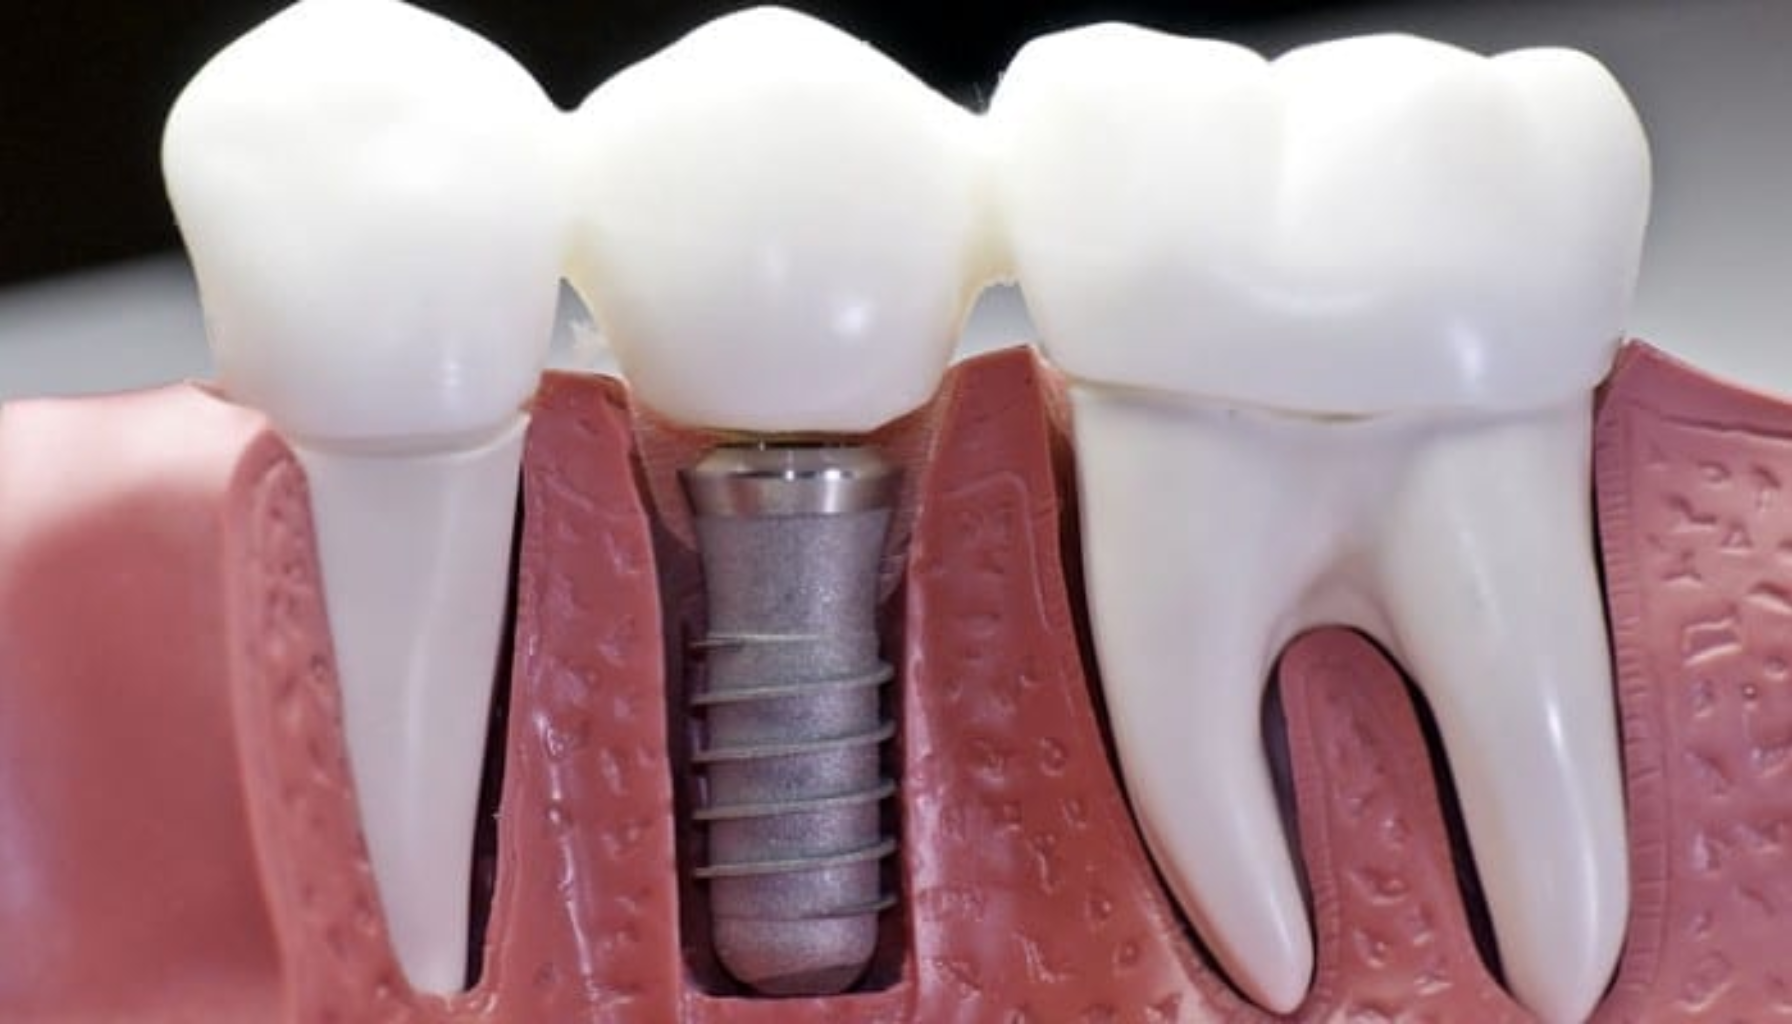

En tann på stift er en tann som har fått en stift satt inn i rotkanalen for å gi den ekstra støtte før den dekkes med en krone. Dette gjøres når tannen er betydelig skadet eller har hatt et rotfylling, men rotkanalen fortsatt er i god stand. Stiften fungerer som et fundament for kronen, som skal beskytte og gjenskape tannen sin opprinnelige funksjon og utseende.

Denne behandlingen kan forlenge levetiden til tannen og er et alternativ til å trekke tannen, som kan føre til behov for mer omfattende behandling som bro eller implantat. En tann på stift kan føles naturlig, ser estetisk ut og er et populært valg for pasienter som ønsker å bevare tannen i stedet for å trekke den.

En tann på stift brukes når en tann er kraftig skadet, ofte etter en rotfylling. Metoden bygger opp tannen med en stift og krone, slik at pasienten kan beholde sin egen tann. Stiften festes i rotkanalen og fungerer som anker for den nye kronen som monteres på toppen.